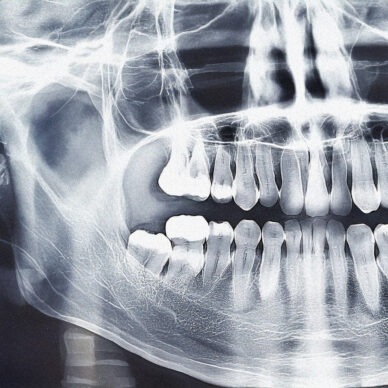

OPG scans gives a full, detailed image of both your upper and lower jaws, teeth, sinuses, and jaw joints (TMJ). This helps your specialist understand your oral health in one go.

By identifying issues that might not be visible during a regular check-up, such as cavities, infections, or bone abnormalities, OPG scans allow for early treatment, preventing bigger problems down the line.

OPG scans are key in planning your treatment like implants, extractions, or orthodontic procedures. With accurate imaging, we can ensure that your treatment plan is tailored specifically to your needs.